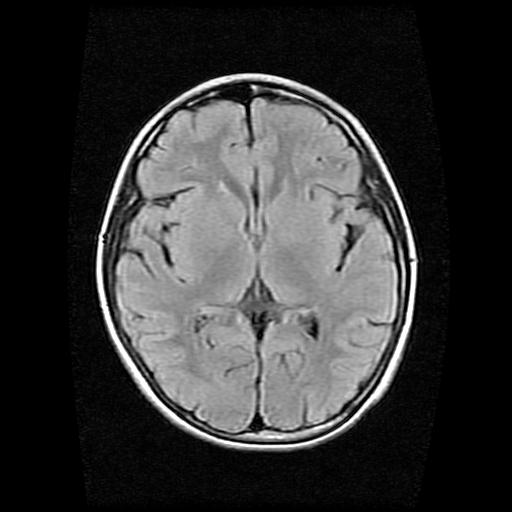

标题: PED0378:女孩9岁,癫痫,看能否停药 [打印本页]

标题: PED0378:女孩9岁,癫痫,看能否停药

9岁女孩,三岁时诊断为癫痫,一直服丙戊酸钠,现患者一般情况良好,家长复查核磁片,看能否停药..

未见异常信号灶.

未发现异常信号。

停药要结合临床,如无发作可以停。